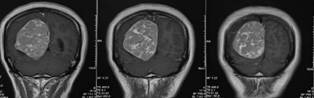

李奇教授与刘鹏程主任医师耐心细致的切除肿瘤